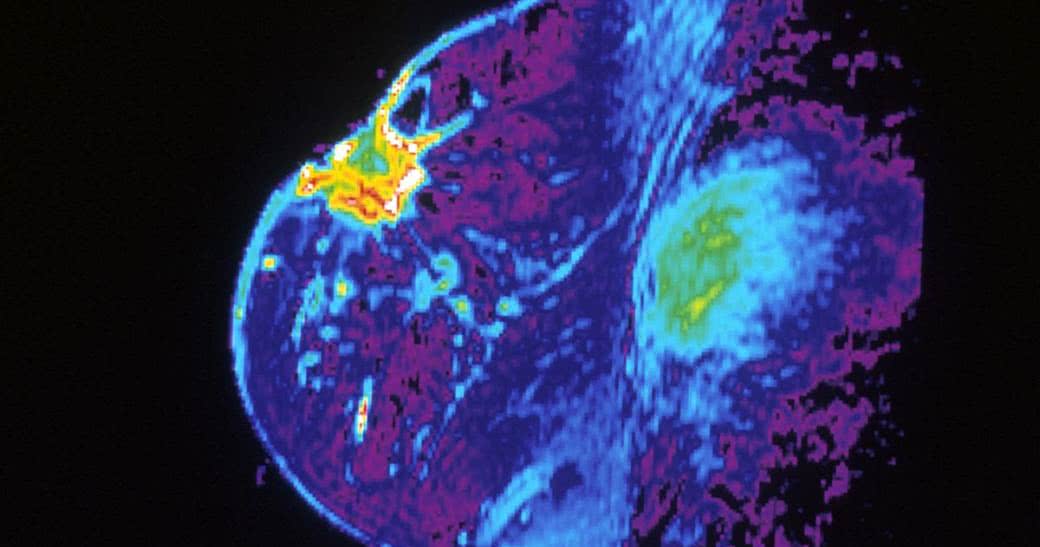

Implanty a rak piersi

Implanty piersi mogą mieć związek z rzadkim typem raka piersi, znanym jako ALCL (chłoniak anaplastyczny z dużych komórek).

ALCL zazwyczaj umiejscawia się w węzłach chłonnych. Wyjątkowo rzadko, niemal nigdy nie zdarza się w piersi. Jednakże na przestrzeni ostatnich kilku lat odnotowano 71 przypadków ALCL umiejscowionych w piersi. Podejrzewa się, że ich przyczyną były wszczepione implanty.